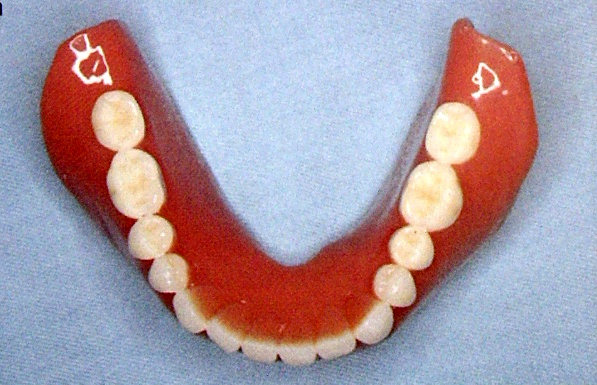

下颌

1.下唇系带(mandibular labial frenum)

下颌正中唇侧粘膜从牙龈交界处到下唇粘膜之间的粘膜皱襞,是口轮匝肌在下颌骨的附着处。

它随唇肌的运动而活动,活动度小于上颌,基托在此区应形成相应的切迹。

2.下颊系带(mandibular buccal frenum)

刃状结缔组织,起于下颌前磨牙牙龈交界线下,呈扇形,其活动度大,抗力强。

基托在此区应形成相应的切迹。

3.颊侧翼缘区(buccal flange area)

又称颊棚区,位于下颌后弓区,在下颌颊系带至咬肌下段前缘之间。

牙槽嵴吸收严重时,此区较为平坦,骨小梁排列与牙合力方向几乎呈直角。

基托可较大范围伸展,稳定义齿

4.舌系带(lingual frenum)

连接口底与舌腹的粘膜皱襞,位于口底中线部,活动度较大。

取印模时应嘱患者将舌向后上方,取功能状态印模。

基托此处作切迹利于固位。